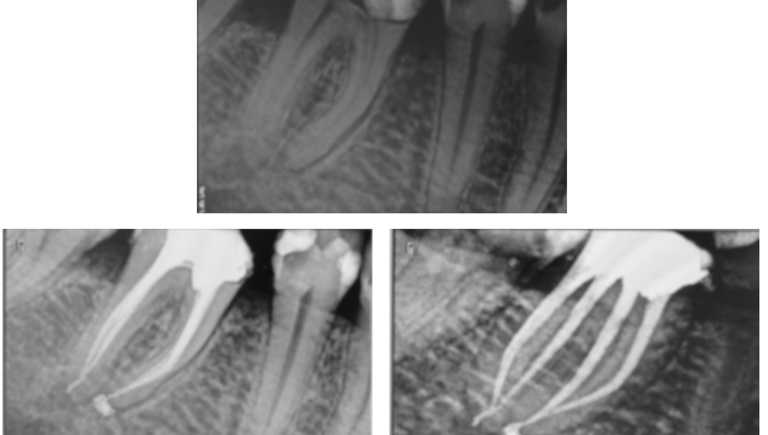

La réalisation du traitement : isolement, mise en forme, irrigation et obturation.

Le suivi : contrôler la réussite à long terme, tant cliniquement que radiographiquement.